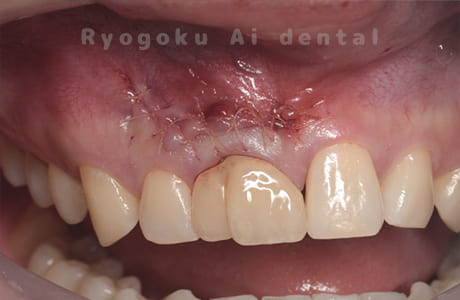

Case07

-

術前

歯根端切除術後

術後1年

- 原因

- 歯根嚢胞

- 治療内容

- 歯根端切除法

- 治療費用

- ¥77,000

他院で行った根管治療後、腫れがひかないためにご来院された患者様です。歯根端切除を行い、現在、経過良好です。

<リスク・副作用>

外科手術のため、術後に出血、痛みや腫れ、違和感を伴います。口腔内の状態によっては適応できないことがあります。歯根端切除で治らなければ抜歯を検討しなくていけない場合もあります。